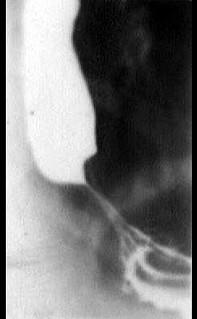

问题 女性病人,20岁,间歇性吞咽困难3年,有时进流质即十分困难,X线检查钡造影如图所示,最可能的诊断是 ( )

选项 A、贲门失弛缓症 B、食管平滑肌瘤 C、贲门癌 D、贲门处憩室 E、食管癌

答案 A